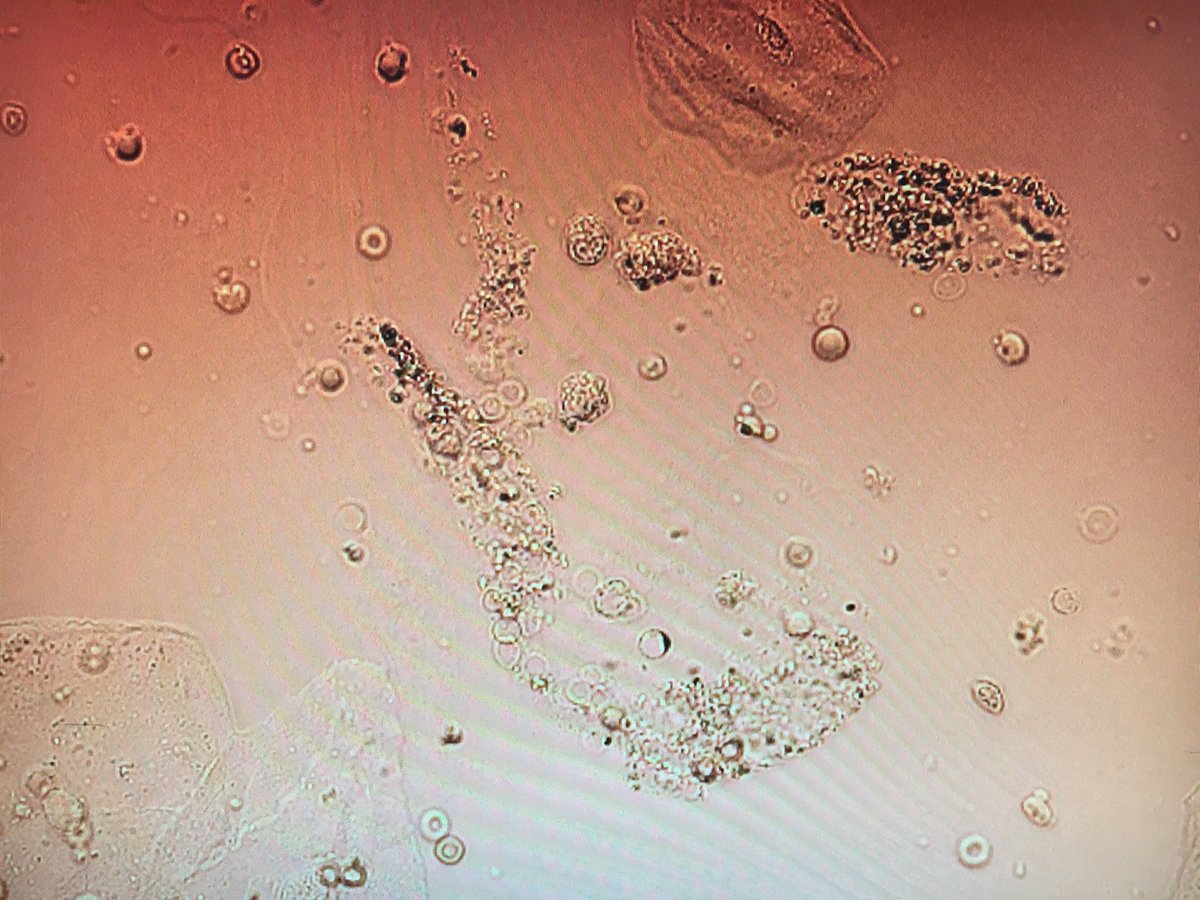

#nephtwitter what’s your#differentialdiagnosis 44 yo male Anemia Hgb 6.7, mild gastropathy on EGD IV heroin use Cellulitis from skin popping Prior endocarditis Hep C antibody + and viral pcr pending Urine sediment pics below pic.twitter.com/wAZS3E7R13

-